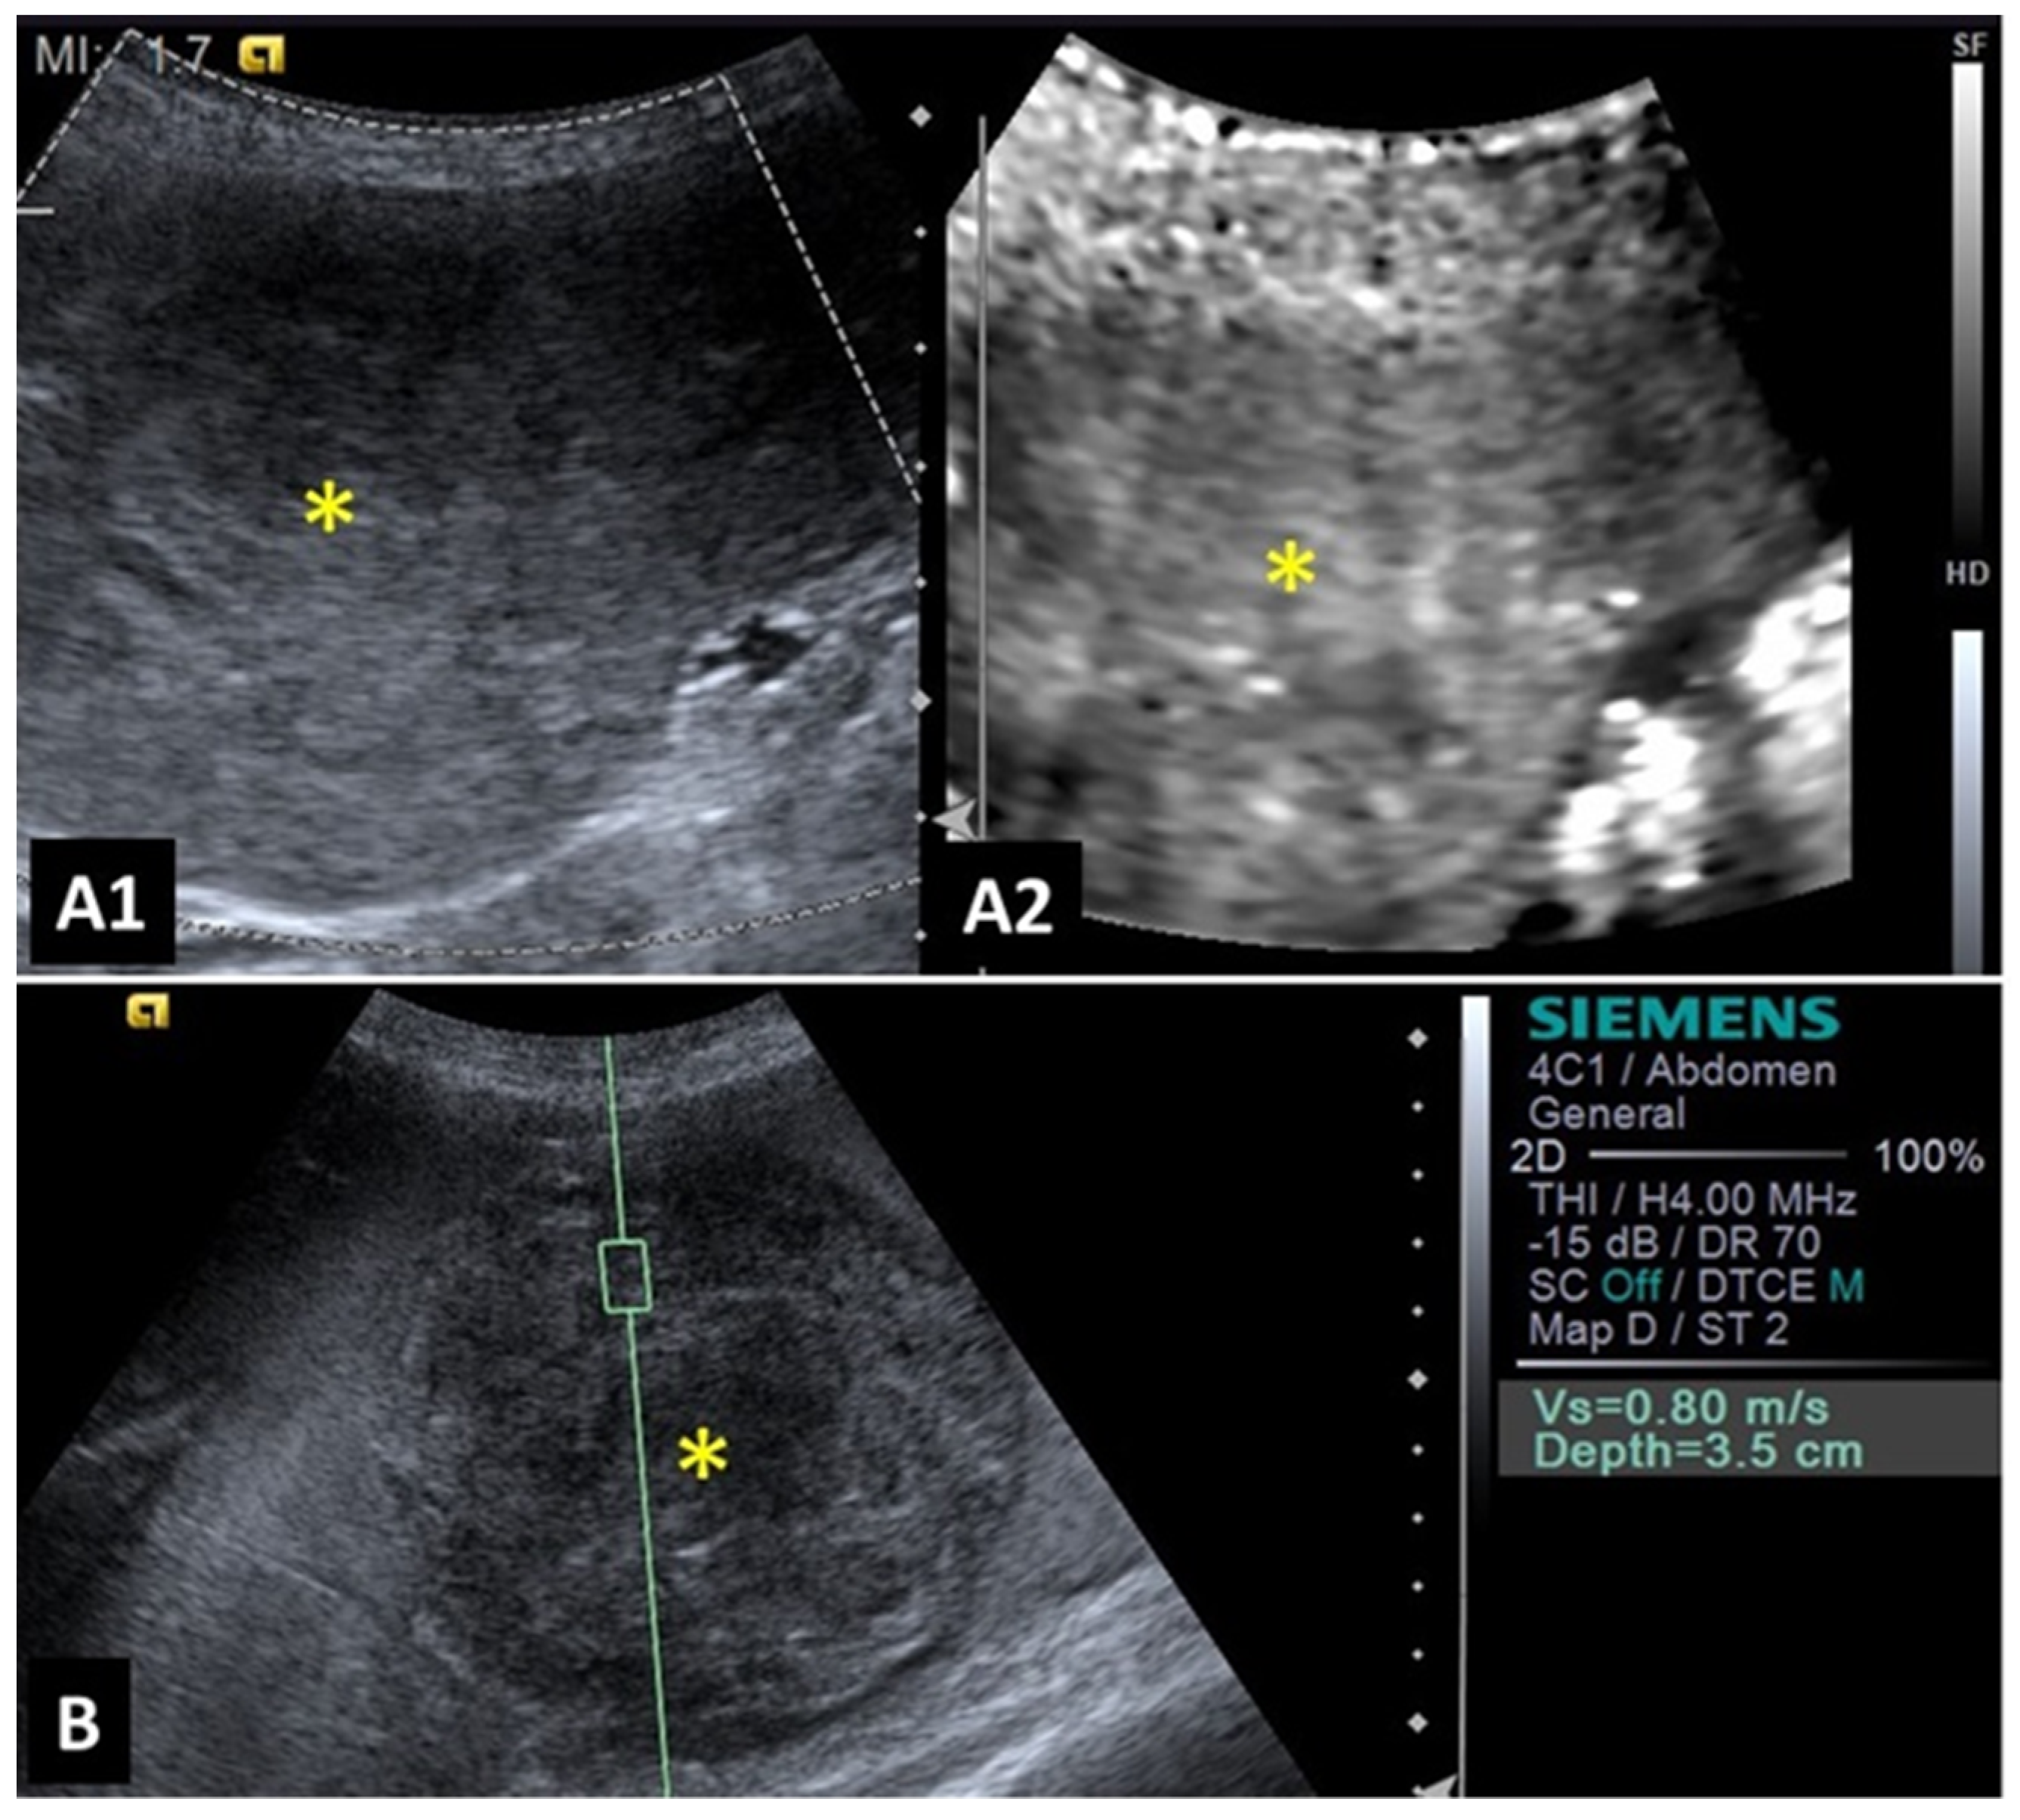

2.3. Spleen

- Maronezi, M.C.; Carneiro, R.K.; da Cruz, I.C.K.; de Oliveira, A.P.L.; De Nardi, A.B.; Pavan, L.; Del’Aguila-Silva, P.; Uscategui, R.A.R.; Feliciano, M.A.R. Accuracy of B-mode ultrasound and ARFI elastography in predicting malignancy of canine splenic lesions. Sci. Rep. 2022, 12, 4252. [Google Scholar] [CrossRef]

- Barella, G.; Lodi, M.; Faverzani, S. Role of strain elastography in differentiating malignant hypoechoic splenic lesions in dogs: Preliminary results. Bulg. J. Vet. Med. 2017, 20, 255–263. [Google Scholar] [CrossRef]